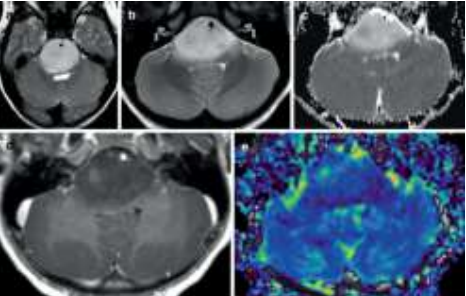

Criança de 7 anos, com histórico recente de diplopia por alteração da mobilidade ocular extrínseca foi encaminhada para realização de ressonância nuclear magnética de crânio em contexto de investigação diagnóstica, apresentando a seguinte imagem:

Enunciado 3027981-1

Baseado nas características epidemiológicas e os achados de seu exame de imagem, e considerando a classificação dos tumores do sistema nervoso central da OMS (2021), assinale a alternativa correta.